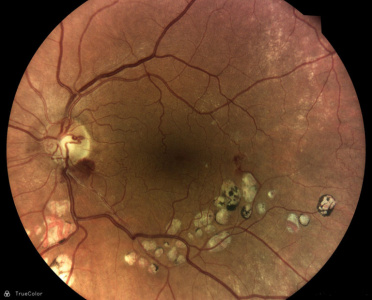

Z vysoko kvalitných fotografií očného pozadia zaobstaraných technológiou iCare DRSplus diagnostikuje diabetickú retinopatiu pomocou umelej inteligencie. Efektívny skríning vyhodnotený softwarom využívajúcim umelú inteligenciu iCare RETCAD®, je schválený pre klinické použitie a je klasifikovaný podľa certifikácie CE (0344) ako zdravotnícky prostiriedok triedy IIa, ktorý šetrí drahocenný čas ako lekára, tak aaj pacienta, umožňuje včasnú intervenciu a pomáha poskytovať včasnú starostlivosť. Analýza pomocou iCare RETCAD® nenahradzuje vyšetrenie zdravotného stavu očí.

AI (umelá inteligencia) okamžite rozpozná práznaky diabetickej retinopatie a klasifikuje výsledky podľa závažnosti na základe medzinárodných klasifikácií. Získate prehľad s hodnotením závažnosti záchytu, kde po analýze snímok zachytených kamerou iCare DRS Plus je automaticky generovaný report o pacientovi so stupnicou závažnosti pre diabetickú retinopatiu na základe medzinárodných štandardov (ICDR, AREDS).

Fundus kamera iCare DRSplus urobí celkovo 4 vysoko kvalitné True Color snímky (dve z pravého a dve z ľavého oka), ktoré sa automaticky ukladajú na cloud a posielajú sa na spracovanie AI - umelej inteligencii. Report je dostupný ihneď a ten je možné prekonzultovať s pacientom počas tej istej návštevy u lekára.